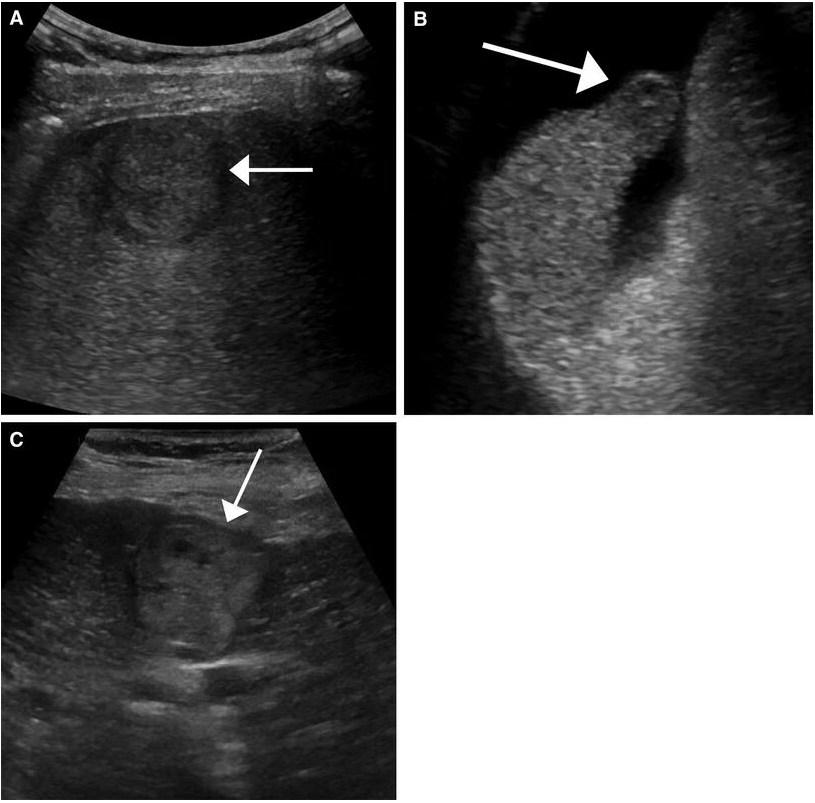

69 M with PMH of HCV cirrhosis & HCC s/p resection in 14 years ago presenting today for a screening ultrasound.

135/73 mmHg / 78 bpm / 16 breaths/min / 96.4°F

sclerae anicteric, no jaundice

CMP wnl, AFP 5